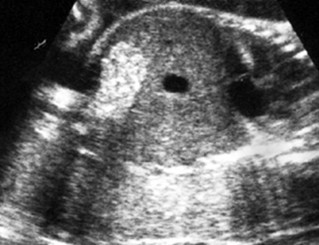

Bebek Beyninde Kist Bebek Beyninde Kist, anne karnındaki bebekler ile ilgili ayrıntılı ultrason sırasında tespit edilen bir problemdir. Gebelikte erken dönemde meydana gelir. Bu kistler; 1) Koroid pleksus denilen yapıların içinde meydana gelir. Koroid pleksus kisti denilir. Beyin gelişimi ilerledikçe küçülür, zaman içinde genellikle kaybolur. Gebeliklerde %1-2 kadar etkili olur. Bu kistler Trizomi 18, Down sendromu gibi bozukluklarda büyük ve düzensiz şekillerde görülür. Böyle bir durumda beb...

Devamı